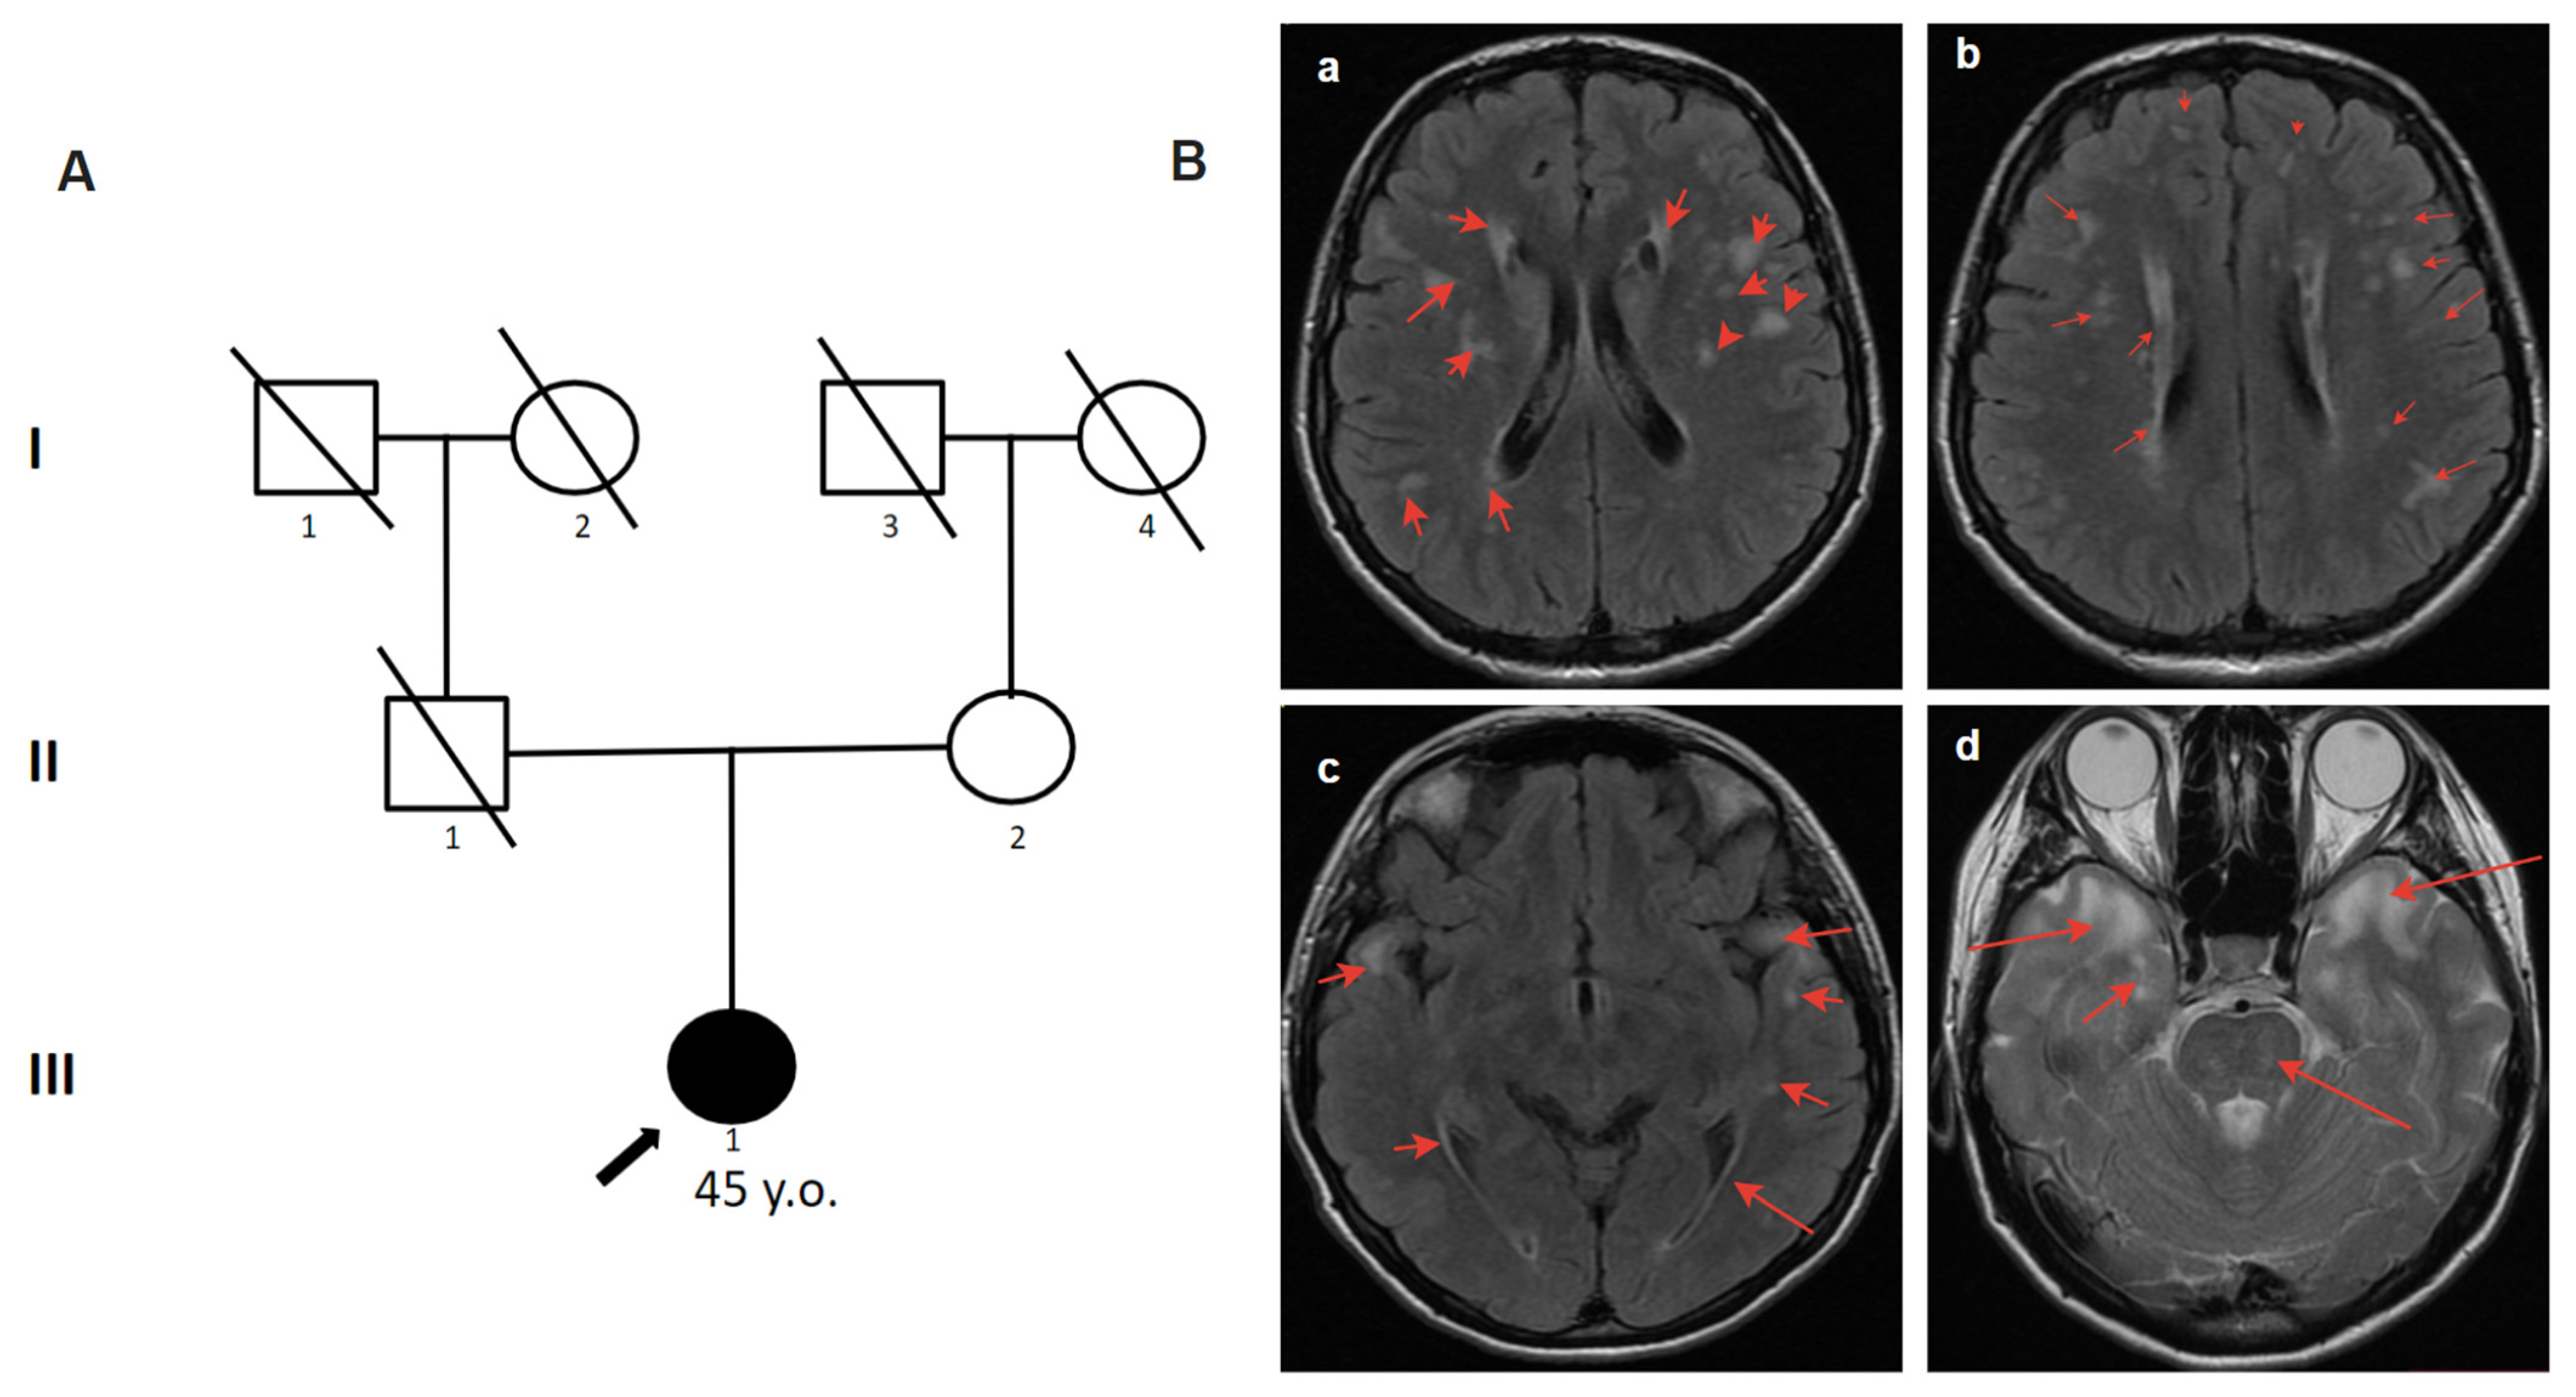

2.4.2. Patient 2

The 45-year-old woman complained of periodic numbness of the left side of the trunk, labile systolic blood pressure, and anxiety attacks in a confined space [6]. The first symptoms started at the age of 22. She was hospitalized at the age of 38 with suspected acute cerebral circulation disorder due to speech impairment and weakness in the right extremities. She was examined by a neurologist at the Multiple Sclerosis Center where CADASIL was suspected. Multiple differently shaped (2–15 mm) irregular white matter hyperintensities (WMH) with clear contours on T2-weighted MRI images were identified. Vast, confluent areas of WMH were detected in symmetrical parts of the temporal lobes without the involvement of the cerebral cortex (Figure 2). The father had a “microstroke” at the age of approximately 50 and another with lethal outcome at the age of 59. According to the patient, the father had no headaches, migraines, or dementia. By partial analysis of the NOTCH3 gene, the canonical splice-site substitution c.341-1G>C in the heterozygous state was detected (Table 1). In this case, bioinformatic analysis using numerous algorithms for predicting splicing disorders (SpliceAI, SPiP, MMSplice) demonstrates a high degree of influence of the c.341-1G>C variant on the splicing acceptor site of intron 3 of the NOTCH3 gene, which disrupts its highly conserved dinucleotides. The peculiarity of clinical manifestations, specific changes on brain MRI, and the identification of a likely pathogenic variant in the NOTCH3 gene allowed us to confirm the diagnosis to the patient. The family history revealed that the father had a “microstroke” at age 50 and another fatal stroke at age 59. According to the patient, the father had no headaches, migraines, or dementia. Unfortunately, in this case, it cannot be determined whether the variant was inherited or arose de novo.

Figure 2.

Pedigree and Neuroimaging features of patient 2. (A)—Pedigree of patient 2.; (B)—MRI images of the brain (III-1), red arrows show: (a,b)—multiple differently shaped (2–15 mm) irregular white matter hyperintensities (WMH) with clear contours on T2-weighted MRI images; (c,d)—vast, confluent areas of WMH in symmetrical parts of the temporal lobes without the involvement of the cerebral cortex.

In the diagnosis of CADASIL, instrumental findings outperform clinical findings. Typical manifestations on MRI include WMH and lacunar infarcts. WMH is a common and early MRI feature of CADASIL. Increased signal intensity in the anterior temporal lobe has high sensitivity and specificity in most cases [15]. This change was detected in two of our patients (patients 1, 2). Signs of recurrent cerebral microbleeds (cortical–subcortical regions, white matter, thalamus, pons) are identified in most patients with CADASIL and are usually localized outside ischemic foci, which allows for considering it almost a pathognomonic sign of the disease [16]. These signs were also present in our patients (patients 1, 2, 3, 4.1). Symmetric periventricular WMH, commonly affecting the anterior temporal lobe, can be observed long before the first symptoms appear [17,18]. By the age of 35, essentially all patients with CADASIL have abnormal MRI findings, which occasionally may occur in the absence of clear clinical features [19,20]. A detailed study of the family history plays an important role in the diagnosis of CADASIL. As stated in patient 1, the key to the diagnosis was a family history. Some patients with a molecularly confirmed diagnosis may remain asymptomatic for a long time, even with well-defined lesions on brain MRI. Brain MRI may be normal early in the disease course, but by the fifth decade, significant white matter changes are the rule rather than the exception [21]. In a study of a cohort of 301 CADASIL patients, it was found that higher WMH associated with the temporal lobes and frontal gyri correlated with a milder course of the disease as compared with WMH in the pyramidal tracts [22]. However, the question of correlation between the degree of WMH changes and the severity of CADASIL patients remains open today and requires further study.